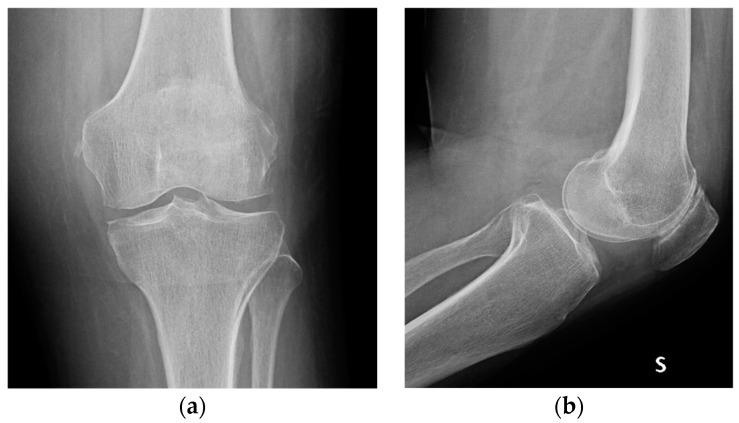

Arthroscopic Debridement Enhanced by Intra-Articular Antibiotic-Loaded Calcium Sulphate Beads for Septic Arthritis of a Native Knee Following Iatrogenic Joint Injection: A Case Report.

Septic arthritis (SA) represents an orthopedics urgency and mainly affects the knee joint. Due to its devastating effects on cartilage, immediate management is crucial. SA is characterized by an annual incidence of 2 to 10 cases per 100,000 individuals, with mortality rates fluctuating between 0.5% and 15%, with a substantially higher mortality rate observed in older people (15%) in contrast to younger cohorts (4%). The etiology of septic arthritis is multifactorial: a spectrum of Gram-positive and Gram-negative bacteria can contribute to the development of this condition, especially . The treatment involves urgent (arthroscopic or arthrotomic) debridement associated with adequate antibiotic therapy. Intra-articular antibiotic carriers can also be used to increase their local concentration and effectiveness. The case of a 67-year-old woman affected by knee SA from methicillin-susceptible is presented. She was treated with an arthroscopic debridement enhanced by intra-articular antibiotic-loaded calcium sulphate beads, together with antibiotic therapy. At 2-year follow up, the infection had been eradicated and the patient fully recovered. This is the first description, to our knowledge, in the English literature, of the use of antibiotic-loaded calcium sulphate beads as an adjuvant in the surgical treatment of SA of a native knee joint.